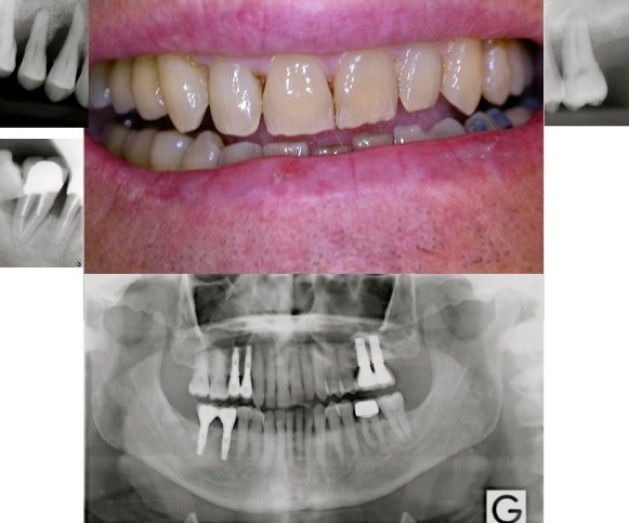

Parodontite = perte d’attache ( os , gencive, ligaments , cément radiculaire) , partiellement réversible par traitement non chirurgical ( détartrages et surfaçages radiculaires ) ou chirurgical et reprise correcte de l'hygiène dentaire et maintenance parodontale régulière . La perte osseuse horizontale est irréversible. On peut régénérer l’os partiellement dans le cas des lésions osseuses verticales.

Si la maladie parodontale n’est pas traitée l'évolution est vers la perte dentaire.

Pour certaines dents il faut prendre la décision d’extraction et remplacement par des implants , avant que la résorption osseuse soit trop avancée.

5.implants pour remplacer les dents irrécupérables

Exemples: